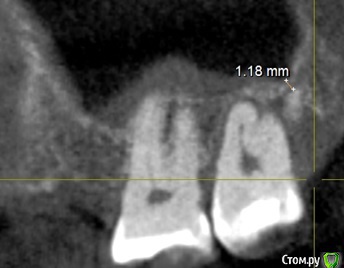

Slavik111 Опубликовано 5 декабря, 2014 Поделиться Опубликовано 5 декабря, 2014 Мужчина 52 года.Несколько лет назад прорезался зуб слева сверху, и стоматологи определяют его как некомплектный 33-й. В этом ряду уже не хватало давно потерянных 4,5,6. Зуб вылез за 8-м.Сейчас он подвижен - если пошевелить пальцем, десна вокруг периодически болезненна.Советуют удалить.Только что сделали 3-Д томографию Сироной по поводу пазух, я посмотрел - под корнем этого зуба неожиданно тонкий промежуток до пазухи - до 1.17 мм на фото.У меня уже есть хронический синусит, так что я боюсь если мне этот зуб просто так выдерут, может образоваться свищ. ВОПРОС: Можно ли просто выдрать? Hадо ли настаивать на ушивании лунки или даже лоскутной операции ? (мне так делали с 6-м справа, там вообще он в пазуху торчал) Ссылка на комментарий

diesel87 Опубликовано 5 декабря, 2014 Поделиться Опубликовано 5 декабря, 2014 Толщины кости достаточно чтобы не получить перфорацию, не вижу сложности. 3 Ссылка на комментарий